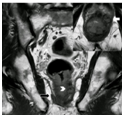

T2加权像粘液性肿瘤呈明显高密度信号,外周蕾丝样增强。MRI检查缺点如下:粘液性肿瘤弥漫性浸润生长已传播至肠壁外,而肠壁解剖结构仍完整;放化疗后即便已无肿瘤、唯留粘液湖时,粘液性肿瘤仍倾向于保持高密度信号(图8);粘液性肿瘤T2加权像呈水样高密度信号,而周围盆腔脂肪也是高密度信号,因此薄层高分辨非压脂轴位T2加权像很易漏诊,此时需调整MRI参数,采用T2加权压脂像抑制脂肪信号,或非压脂轴位T2加权像采用二种不同高回波时间(TE)检测肿瘤,因为周围盆腔脂肪产生二种不同的密度信号(图9)。

图8  65岁女性直肠粘液腺癌放化疗后,轴位T2加权像显示直肠壁粘液池高密度信号(长箭头)和直肠系膜淋巴结(箭头),较前无显著变化,临床定义为无治疗反应,但术后病理证实为粘液池,未见肿瘤细胞。

图9  直肠粘液腺癌。TE 80ms(9A)和120ms(9B)轴位T2加权像显示直肠腔内粘液腺癌不同的高密度信号(星号),右侧肠壁(箭头)和左侧直肠系膜(长箭头),二种TEs信号差别有助于肿瘤检测。9C显示轴位T2加权压脂像,方便检测肿瘤(星号)和肿瘤播散(长箭头)。